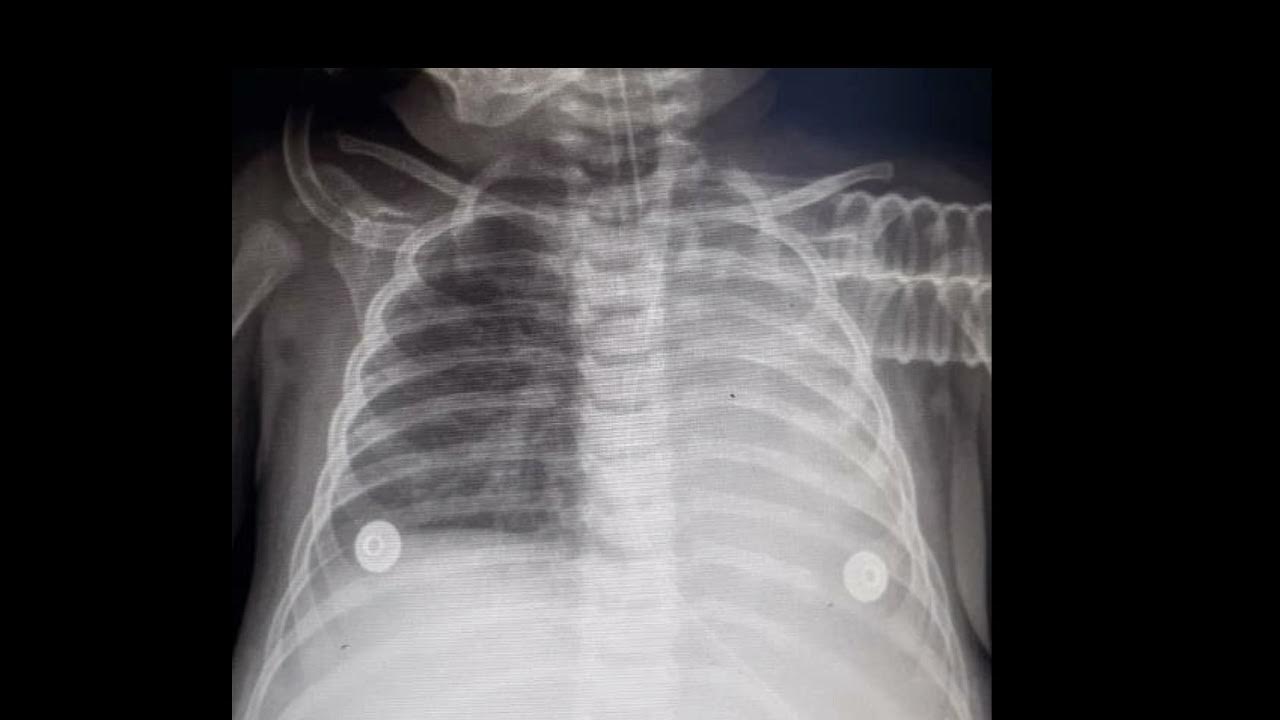

Common causes of unilateral white out lung 🫁in CXR ,pneumonia, pleural What Causes White Out On Chest X Ray The radiologist who interprets the x. These three causes are extensive pneumonia, collapse. The differential diagnosis can be shortened further with one simple observation: Collapse (atelectasis) of an entire lung; This patient had a chronic disease with progressive consolidation. A white spot amidst the normal black lungs can therefore be a cancer, infection, bleeding, fluid, foreign body amongst other possibilities.. What Causes White Out On Chest X Ray.

What is the cause of this "white out" on the right side of the chest x What Causes White Out On Chest X Ray The radiologist who interprets the x. The differential diagnosis can be shortened further with one simple observation: Within one week, alveolar pulmonary edema (hyaline. These three causes are extensive pneumonia, collapse. A white spot amidst the normal black lungs can therefore be a cancer, infection, bleeding, fluid, foreign body amongst other possibilities. This patient had a chronic disease with progressive. What Causes White Out On Chest X Ray.